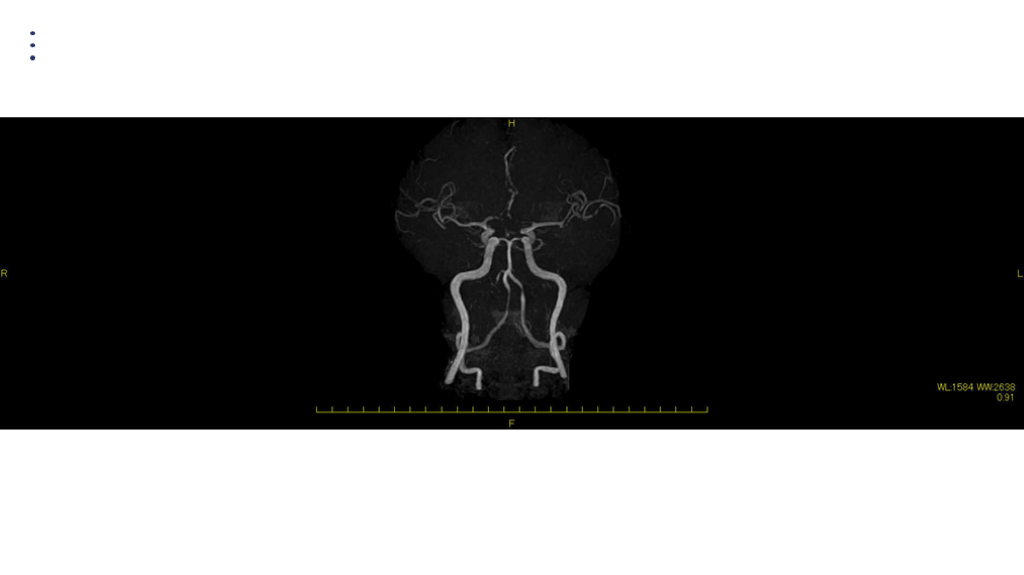

MRA DAY2

画像 所見 DAY 14 MRA 悪化